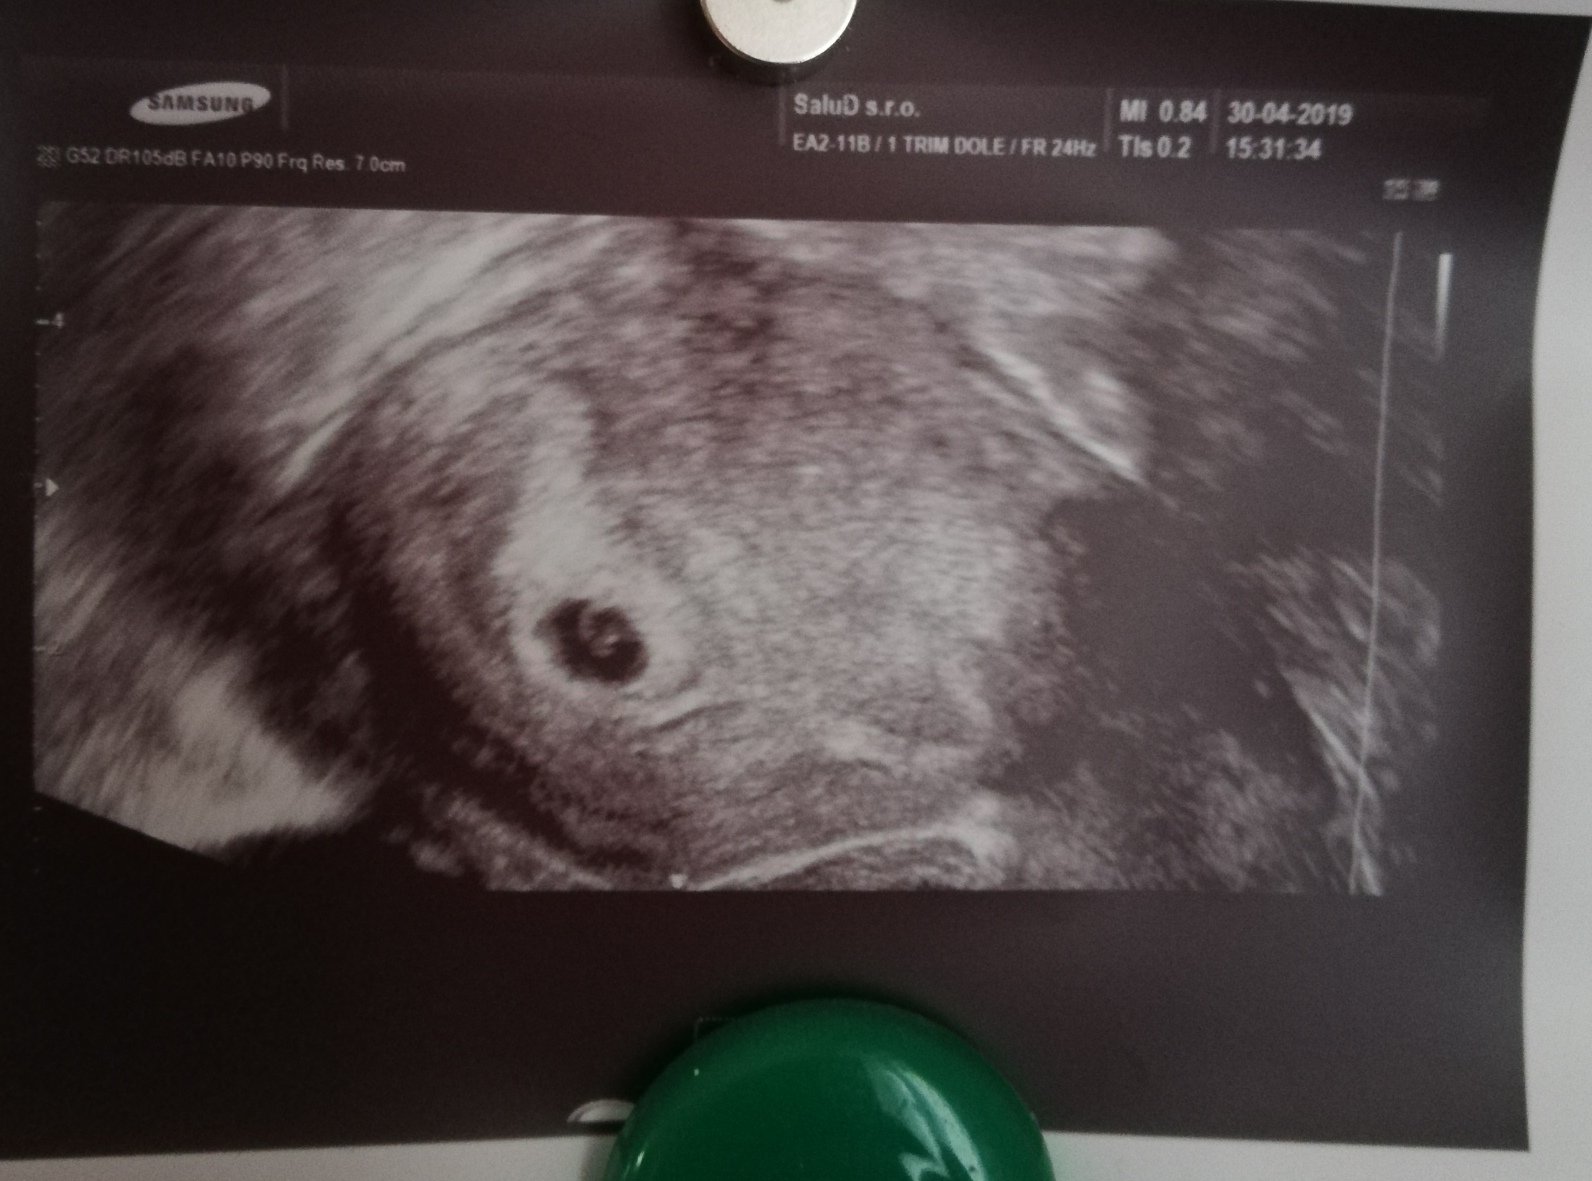

@ingelika78 ďakujem za milé slová......my už aj sme 🙂 síce ešte krátko ale tak dúfam, že všetko dobre dopadne...

@ingelika78 naša fazuľka 🙂